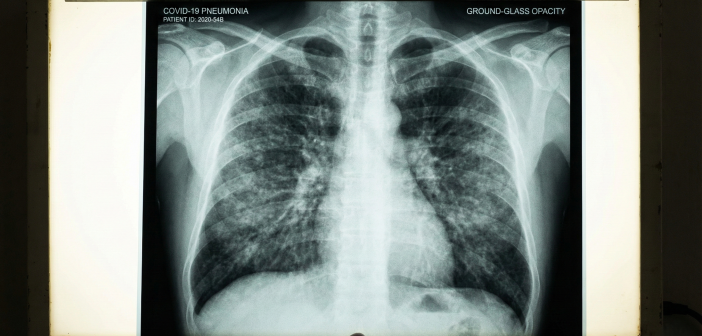

Симптоматика, с которой пациенты обращаются за помощью, напоминает неудачный гибрид нескольких инфекций. Врачи отмечают нехарактерное для респираторных заболеваний сочетание: наряду с классическими признаками поражения легких — одышкой и падением сатурации — у больных наблюдаются кожные высыпания, схожие с ветряной оспой или энтеровирусной экзантемой. Однако, в отличие от детской ветрянки, этот вирус (или вирусный коктейль) демонстрирует агрессивную тропность к легочной ткани. Воспалительный процесс стартует молниеносно, часто минуя стадию легкого недомогания, и за считанные дни приводит к обширному поражению паренхимы.

Эксперты связывают диагностические трудности с природой вспышки. Вероятнее всего, речь идет о сочетанной инфекции — так называемой микст-патологии, когда на организм одновременно атакуют активизировавшаяся микоплазма (Mycoplasma pneumoniae) и сезонные вирусы, включая мутировавшие штаммы энтеровирусов или аденовирусов. Микоплазма, будучи внутриклеточным паразитом, не видна для стандартных вирусных тестов и не реагирует на популярные антибиотики пенициллинового ряда, что объясняет безуспешность домашнего самолечения. Пациенты теряют драгоценное время, принимая препараты, которые не действуют на возбудителя, пока инфекция опускается в нижние дыхательные пути.

Сложившаяся ситуация меняет подход к первичной диагностике. Врачи настоятельно рекомендуют отказаться от тактики выжидания и доверия отрицательным экспресс-тестам. Отсутствие двух полосок на тесте при наличии высокой лихорадки, сыпи и кашля больше не является маркером безопасности. Нынешний эпидсезон диктует новые правила: любое затяжное повышение температуры с респираторными симптомами требует исключения атипичной пневмонии методами компьютерной томографии и специфических анализов крови, а не только мазков из носоглотки. Биологическая реальность такова, что вирусы учатся обманывать нашу бдительность быстрее, чем мы обновляем аптечки, и цена промедления в этот раз измеряется объемом сохранной легочной ткани.